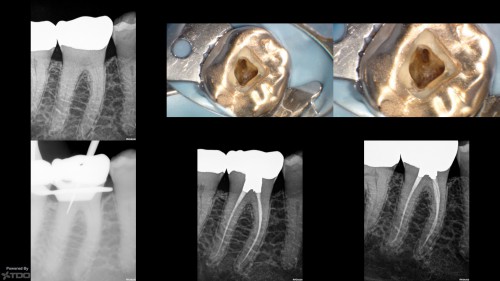

#19 – Re-endo

By Reuben Joseph / October 29, 2018

#19 with  (1)# file in the MB (2) Ledged ML (3) Screw post in the distal. The file […]